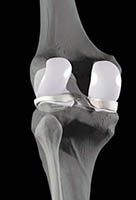

Em lesões que não respondem adequadamente ao tratamento não cirúrgico, necessita-se realização de cirurgia.

As principais modalidades de cirurgia semelhantes àquelas realizadas para o tratamento da cartilagem (veja o artigo “Cartilagem”).